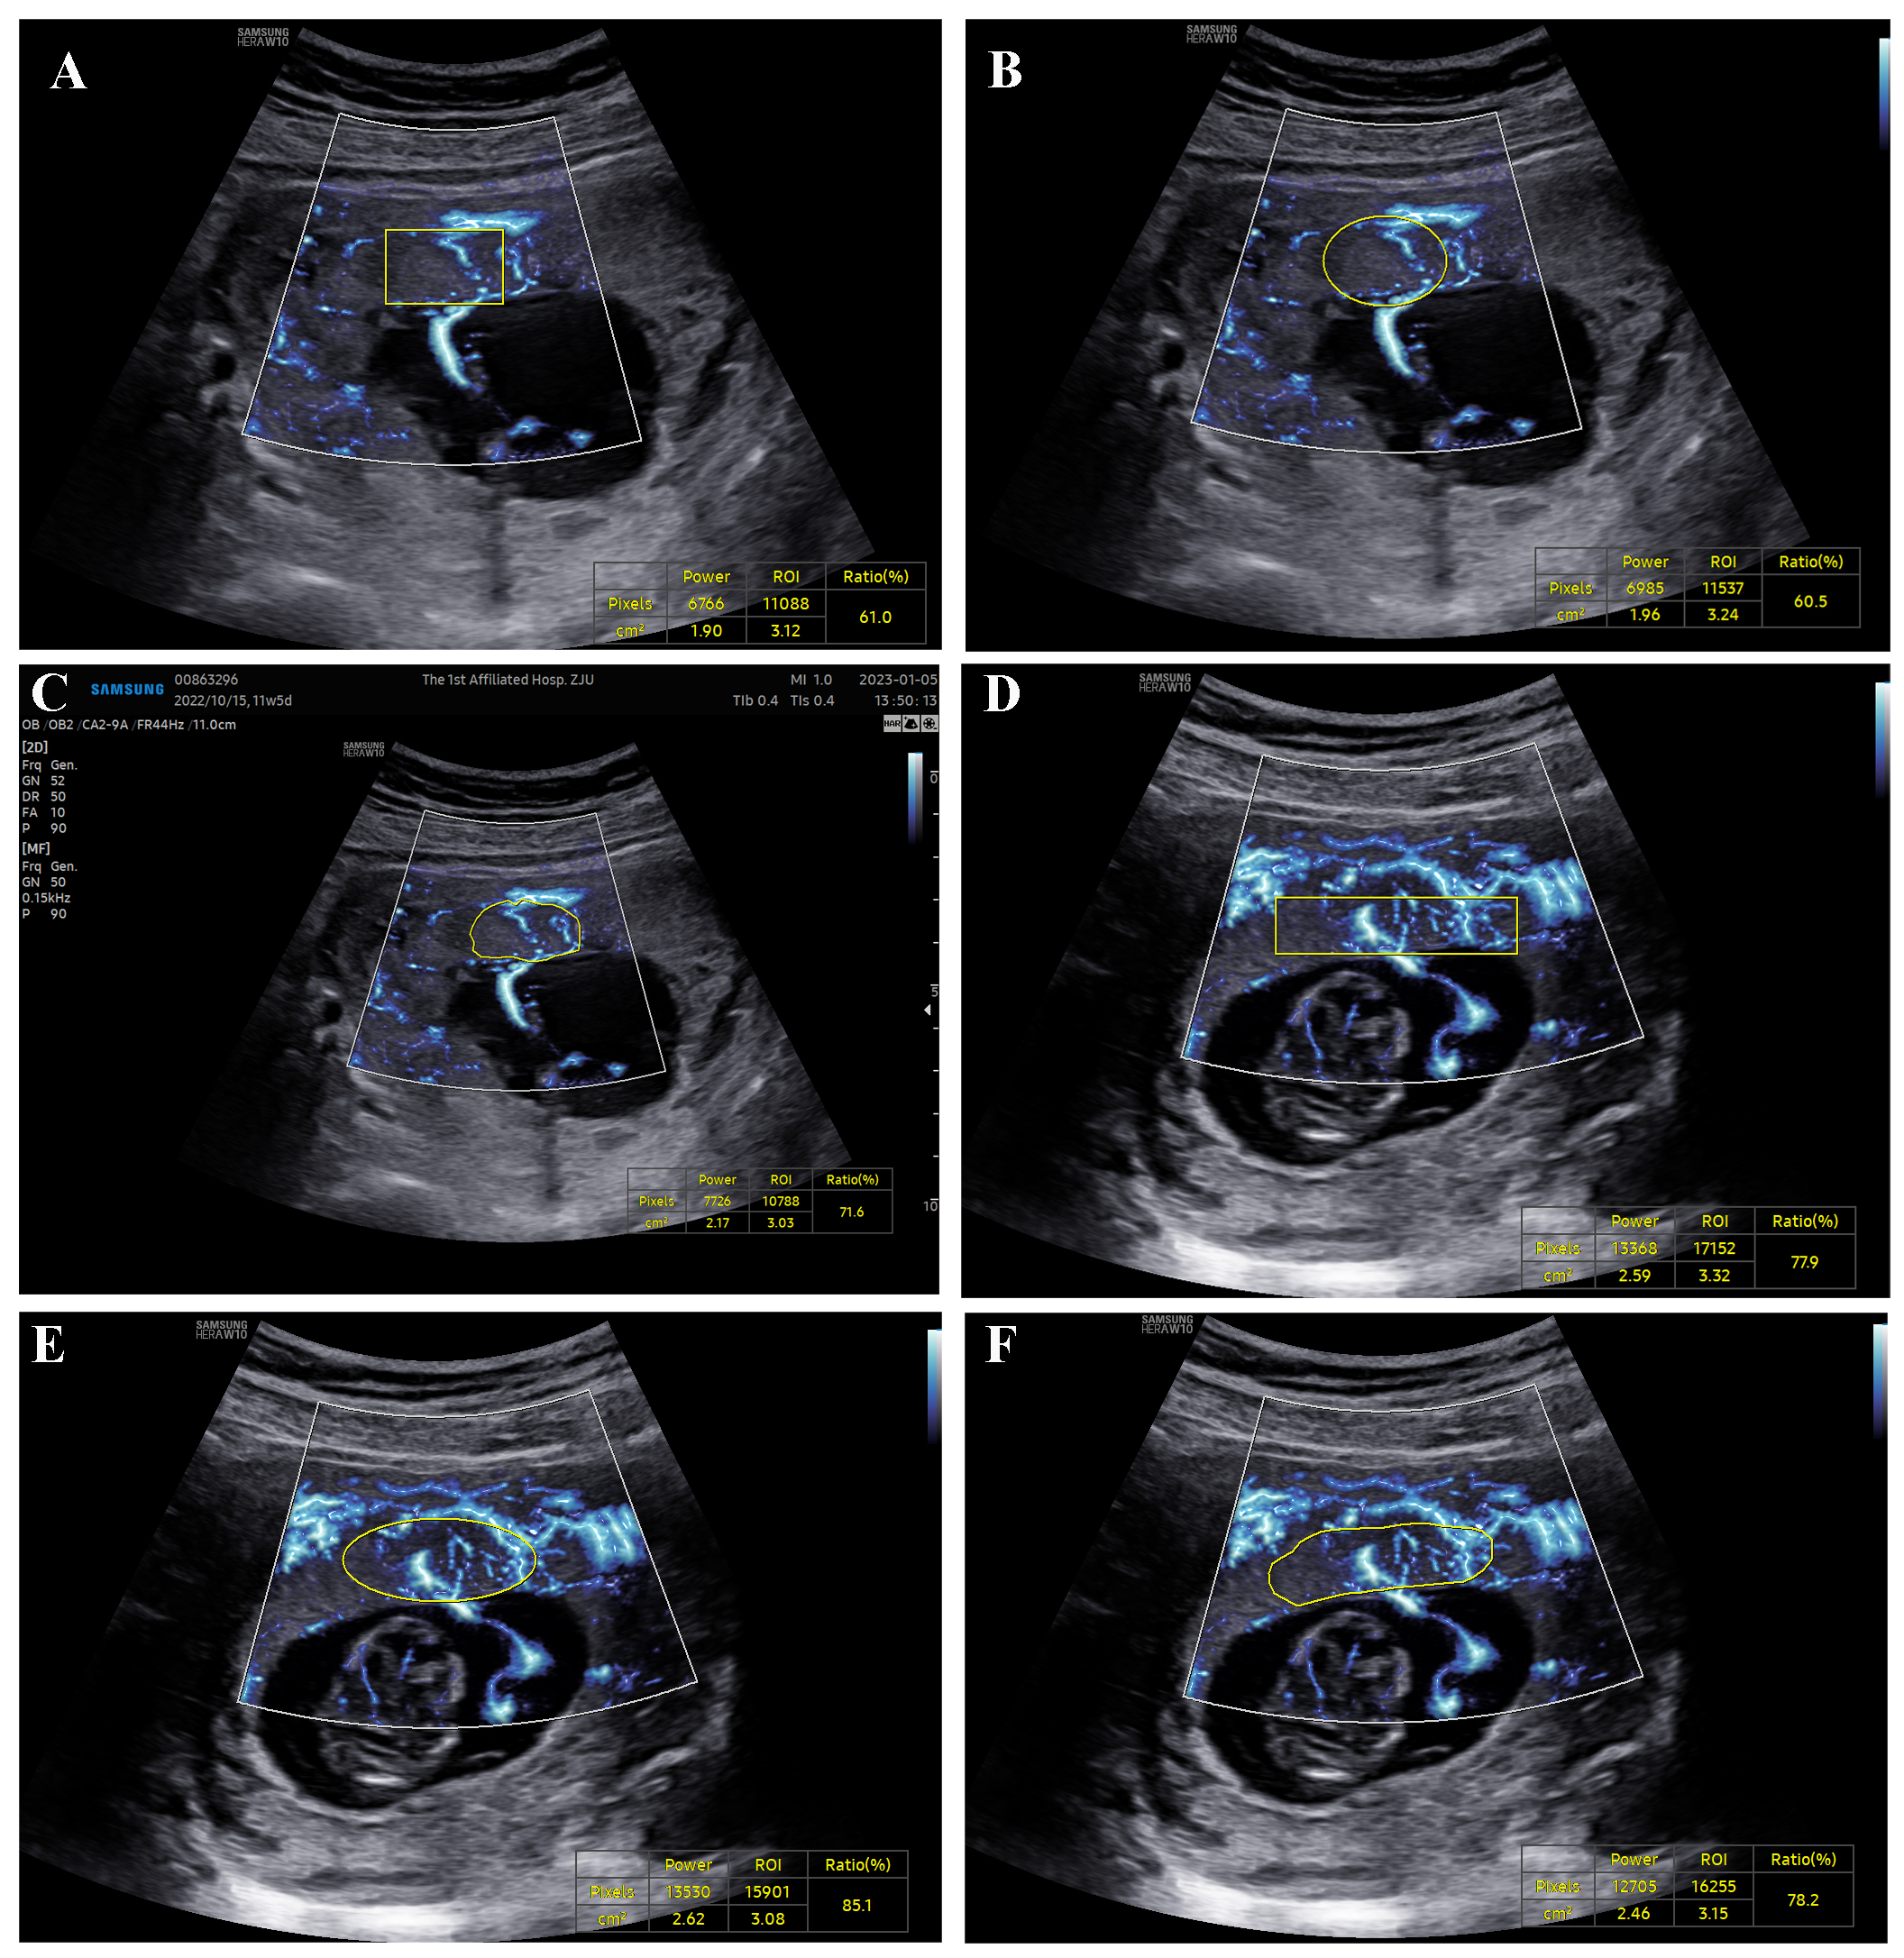

There were no statistically significant differences between the infection group and the normal group in terms of age, gestational age, parity, gestational number, placental position, placental thickness, and other factors (p > 0.05). The VIMV values obtained by elliptical, rectangular, and manual tracing methods at the same placental level in the MV-Flow mode showed no statistically significant differences (p > 0.05). Except for PI of right UtA, The VIMV values and the S/D, PI, and RI of UtA were not significantly different between the infection group and the normal group (p > 0.05). Within the infection group, no significant differences were observed in VIMV value, placental thickness, S/D ratio, PI, RI of UtA, or neonatal weight between the adverse pregnancy outcome good pregnancy outcome group (p > 0.05).

MV-Flow technology can quantitatively evaluate placental microvascular perfusion, and the VIMV is not influenced by the tracing method, making it a reliable indicator for monitoring the intrauterine status of the fetus. No significant differences in VIMV values were observed between the infection group and the normal group. The findings suggest that early infection with the Omicron variant does not impact placental blood perfusion. Infection with the Omicron variant during the first-trimester of pregnancy does not increase the risk of adverse pregnancy outcomes for the fetus. However, further studies are needed to reach a definitive conclusion on this topic.